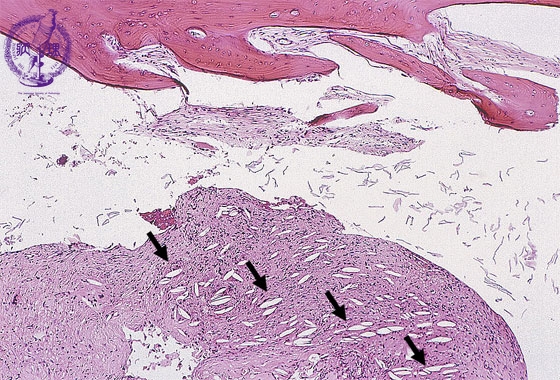

- (1)cholesteatoma, otitis media

Bone fragments and fibrous granulation tissues are seen. Cholesterol clefts are also seen in the granulation tissue (arrow).